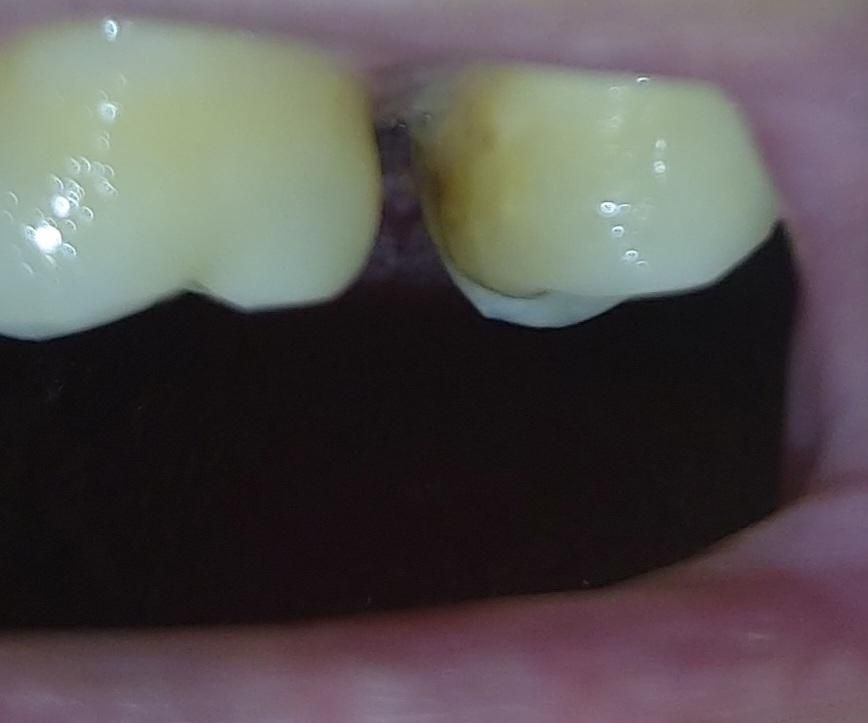

원래는 멀쩡했던 치아인데 왼쪽 아랫어금니가 많이흔들려서 발치했는데 한달정도지나니 이런식으로 왼쪽 윗어금니가 뒤쪽으로 밀려져 벌어졌습니다..

발치하면 원래 위쪽 치아가 밀리나요???

• 1번 째 사진

맞닿는 치아 없어서 정출되면서 치아가 여러 방향으로 이동한 것 같습니다. 더 이상의 정출을 막기 위해 아래 임플란트나 임시틀니를 착용해주거나 아니면 위쪽 인접 치아와 묶는 스플린트 치료가 필요합니다